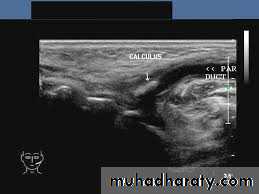

1. For detection of cervical lymphadenopathy.2. Examination of various masses including thyroid gland, abscess, salivary glands.

3. Vascular abnormalities (Doppler US)

4. Aids in differentiation of solid or cystic masses.

5. Valuable for guided fine needle aspiration biopsy (FNA).